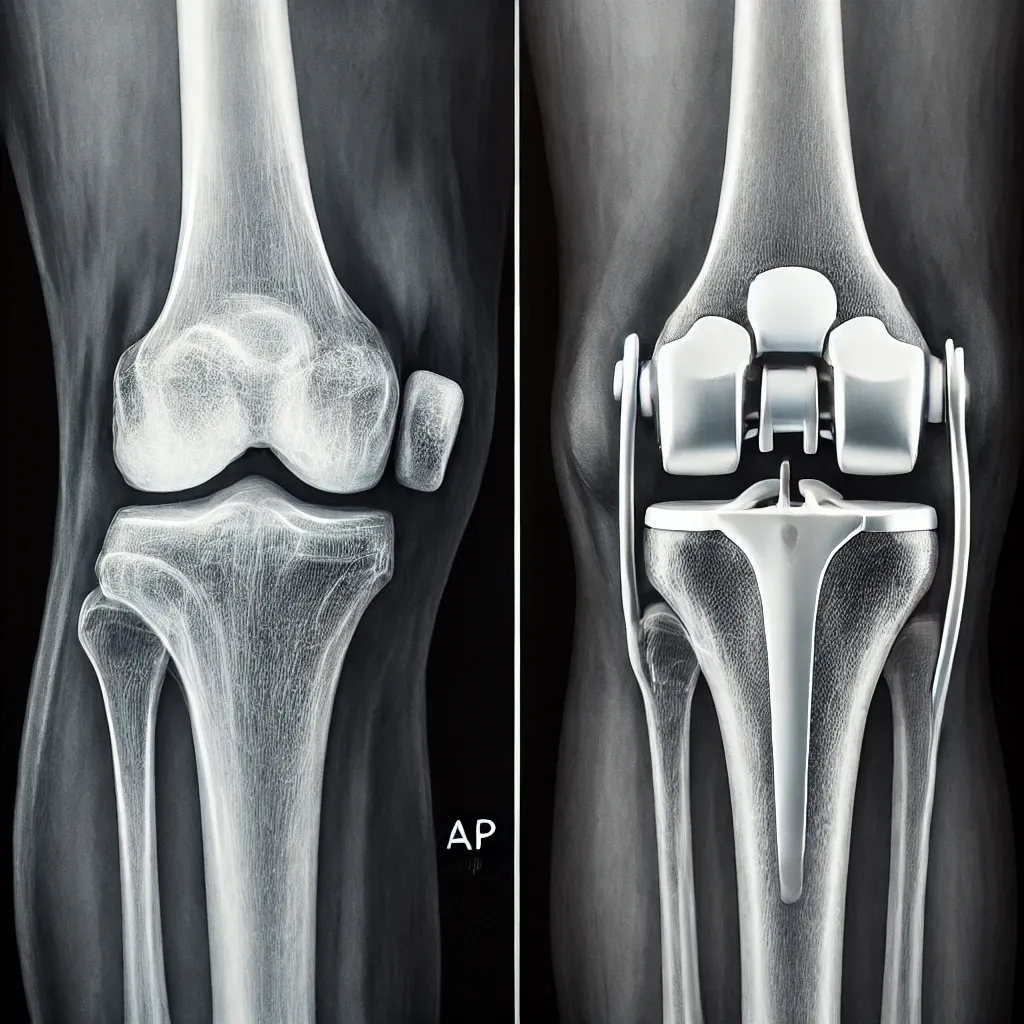

A total knee replacement is a surgical procedure designed to relieve severe pain and restore mobility in people with damaged knee joints. This is often due to arthritis, injuries, or other degenerative joint conditions. The process involves replacing the damaged surfaces of the knee joint with artificial components, typically metal and plastic.

During the procedure, surgeons remove the damaged cartilage and bone from the knee and replace it with a prosthetic joint. The surgery typically takes 1-2 hours, followed by a structured rehabilitation plan to regain mobility and strength.

Can you guess which knee is affected by arthritis?

-The answer is the second picture.